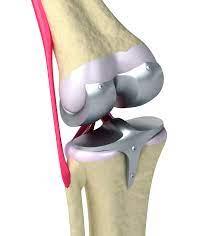

Total knee replacement (TKR) is considered necessa...

What is partial knee replacement surgery? Partial ...